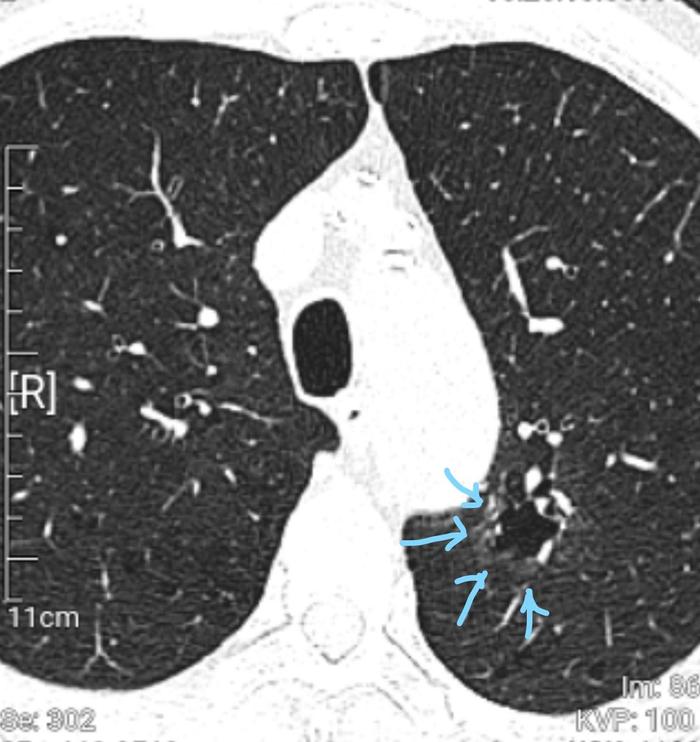

这个混合磨玻璃结节最大径24毫米,以实性成分为主,实性成分位于中心地带。结节的边缘有一些磨玻璃成分,左边两个蓝色箭头和最右边的蓝色箭头指示的是磨玻璃成分。右边数第二个箭头指示的是肿瘤与胸膜之间有线条相连,叫做胸膜牵拉征,这是一个恶性征象。

病理如下:

这也是一个浸润性腺癌,腺泡型为主。